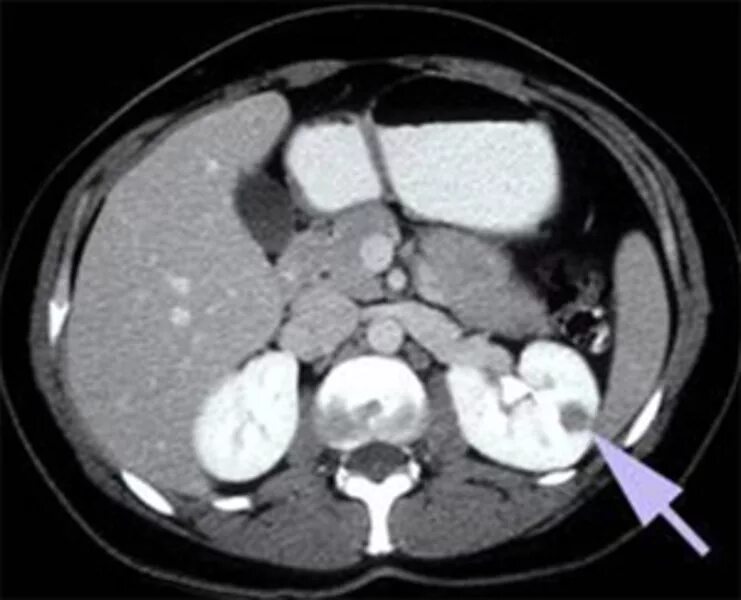

Метастазы рака почки